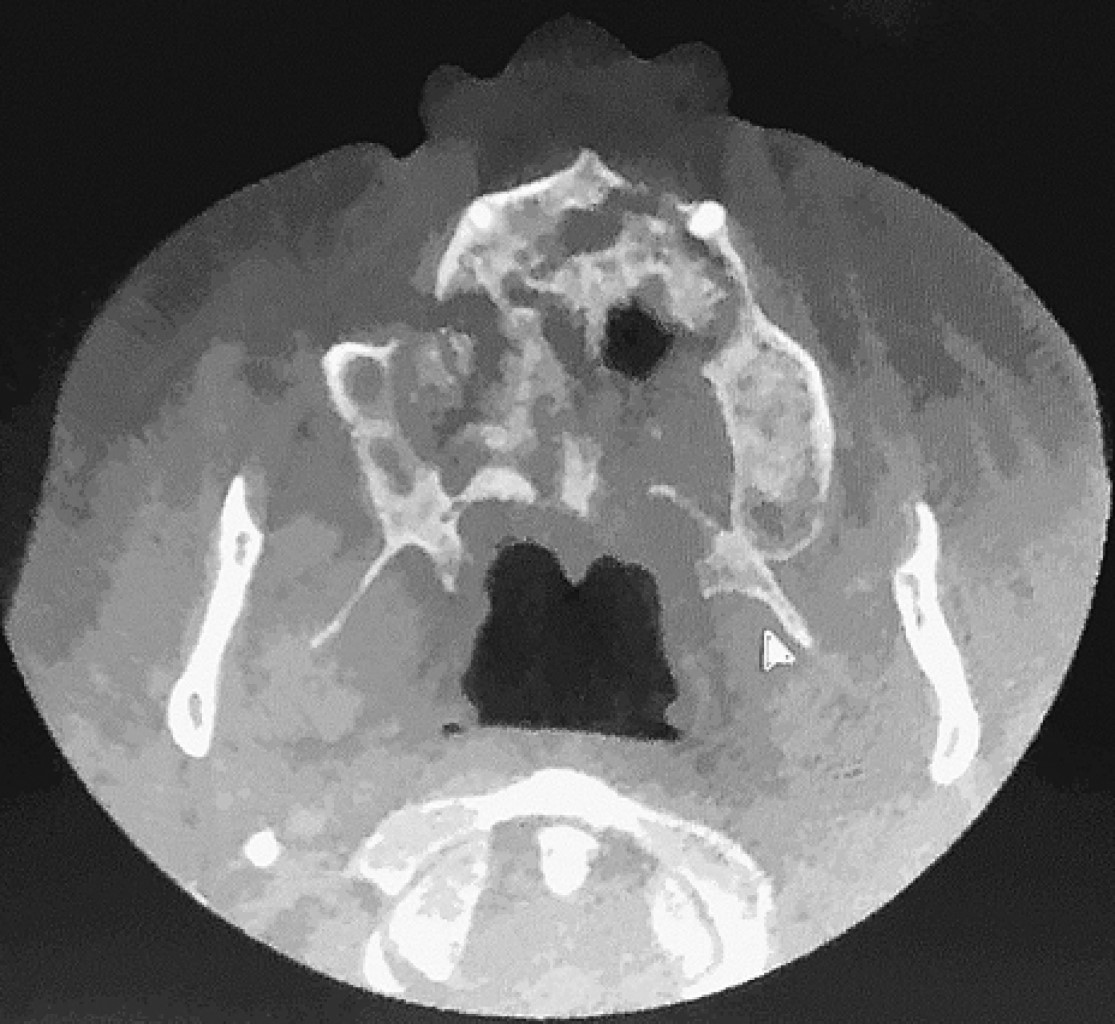

Rhino-orbit-cerebral mucormycosis with palatal manifestation, in a diabetic patient. Apropos of a clinical case and review of the literature

Mucormycosis is a rare, acute and frequently lethal disease caused by aerobic saprofit fungi and opportunists of the Mucoromycotina subdivision (before Zygomicota). Several clinical presentations have been described: rhino-orbital-cerebral, pulmonar, gastrointestinal, mucocutaneous and disseminate, rhino-orbital-cerebral mucormycosis (ROCM) is frequently associated To diabetic patients with inadequate control or hematological diseases. The rhino-orbital-cerebral presentation has a quick development with high morbidity and mortality in immunocompromised patients, with the need of a multidisciplinary medical and surgical approach. Case report of a patient with rhino-orbital-cerebral mucormycosis associated to uncontrolled diabetes mellitus DM2, palatine and cutaneous invasion, who was surgically treated with total bilateral maxillectomy, showed no evidence of recurrency in the next 16 months of follow up.

Figure 1